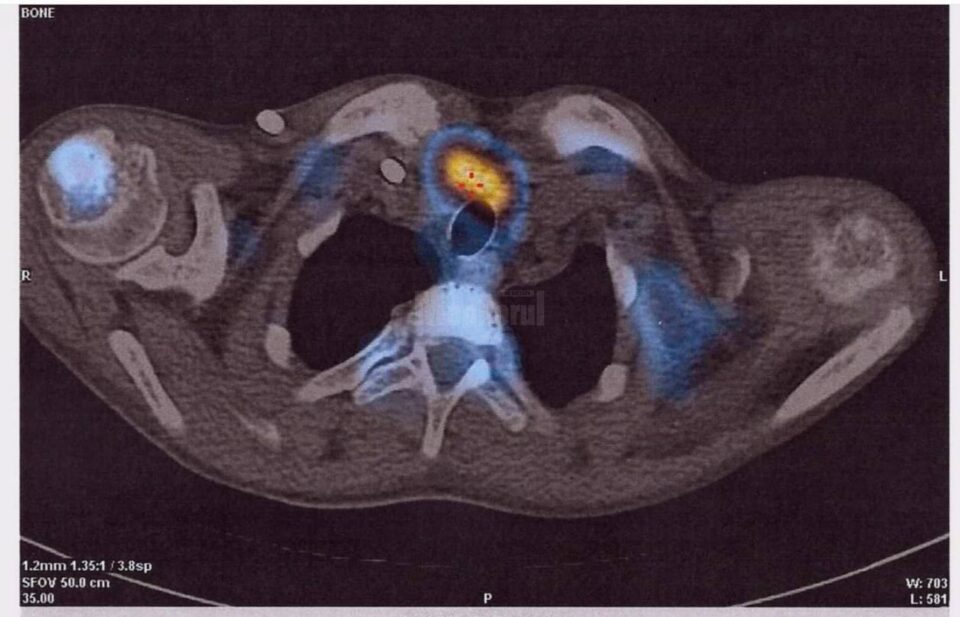

O echipă medicală multidisciplinară formată din dr. Rareș Voinea, dr.Mihaela Guțu, dr. Mihai Guțu, dr. Ionuț Cordoș, dr. Adrian Nistor și dr. Ruslan Gorceag a realizat o nouă premieră la Spitalul Județean de Urgență „Sfântul Ioan cel Nou” Suceava – prima paratiroidectomie subtotală (îndepărtarea unor porțiuni din glandele paratiroide), la un pacient în vârstă de 19 ani. Managerul spitalului, dr. Alexandru Calancea, a transmis, printr-un comunicat de presă, că pacientul a fost diagnosticat la sfârșitul anului 2020 cu boală cronică de rinichi, în stadiul terminal, și era inclus în programul de hemodializă. O complicație frecventă a acestei boli este creșterea glandelor paratiroide, ce determină modificări osoase. „Pe fondul acestora pacientul a prezentat o fractură spontană de col femural, rezolvată prin protezare de către medicul ortoped dr. Rareș Voinea”, a arătat dr. Calancea. Acesta a explicat că evaluarea glandelor paratiroide s-a realizat cu ajutorul medicinei nucleare, de către dr. Mihaela Guțu și dr. Mihai Guțu, prin SPECT-CT, identificându-se astfel cu exactitate locația și mărimea acestora. Ulterior, echipa chirurgicală, formată din dr. Ionuț Cordoș și dr. Adrian Nistor, a efectuat prima paratiroidectomie subtotală la Suceava. Pacientul a fost urmărit în continuare în secția de Anestezie Terapie Intensivă, sub coordonarea dr. Ruslan Gorceag, a mai spus dr. Alexandru Calancea.